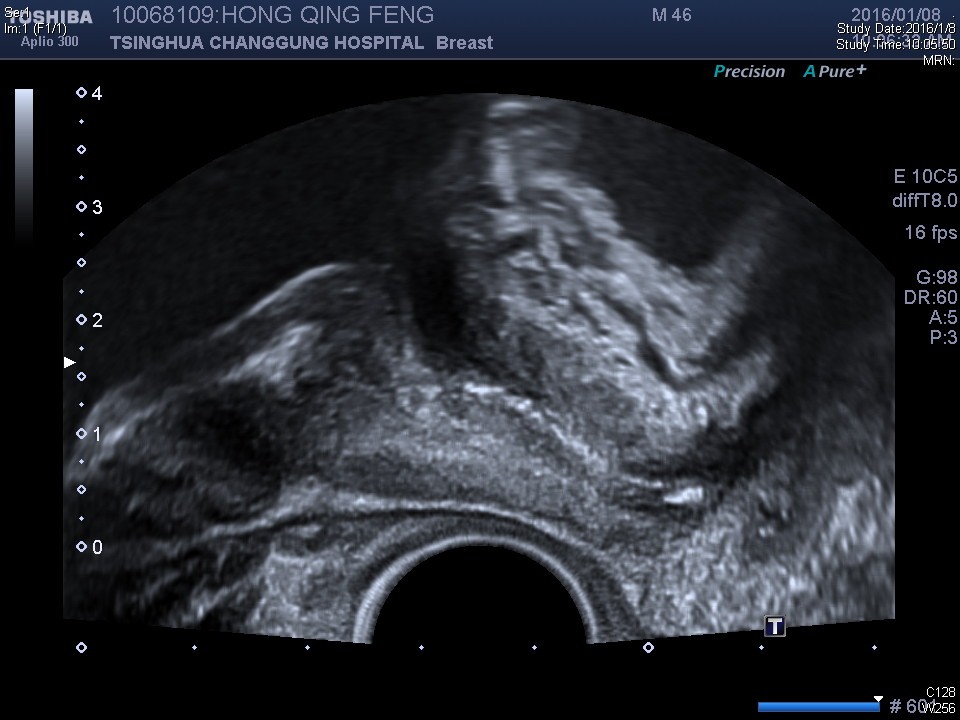

经过4周的康复训练,患者肢体功能明显提高,基本实现康复目标,立位平衡1级,助行器辅助下可独立完成坐站转移,短距离步行,肌肉萎缩减轻。但患者排尿功能无明显改善,自主排尿功能无恢复,手法不能诱发排尿,仍需间歇导尿每日4次,考虑患者有尿道括约肌痉挛,予口服盐酸特拉唑嗪,症状无明显改善,为进一步明确尿道病情变情况,予经直肠超声检查:可清晰显示尿道外括约肌,并提示尿道外括约肌有痉挛,遂于超声引导下尿道外括约肌肉毒毒素注射术,术后第二日,患者手法诱发反射性排尿50ml,术后第六日,患者可在20分钟左右主动排尿约400ml,但由于患残余尿仍在200ml左右,间歇导尿次数减至每日2次,患者拟近期回当地专科医院继续治疗。